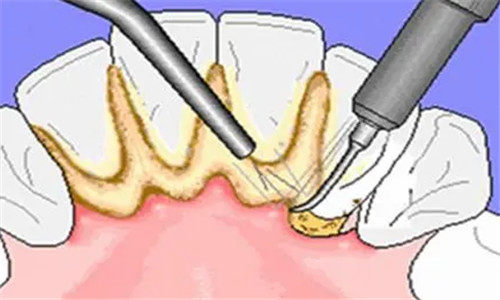

科室将牙周健康管理作为重点,提供从基础清洁到深度治疗的阶梯式服务。

基础护理项目:

超声波洁牙:单次费用区间为62-125元,适配日常清洁;

牙周病治疗:

轻度牙周炎:单疗程费用区间为540-1000元,适配牙龈出血病例;

中度牙周炎:单疗程费用区间为1000-1950元,适配牙周袋形成病例。